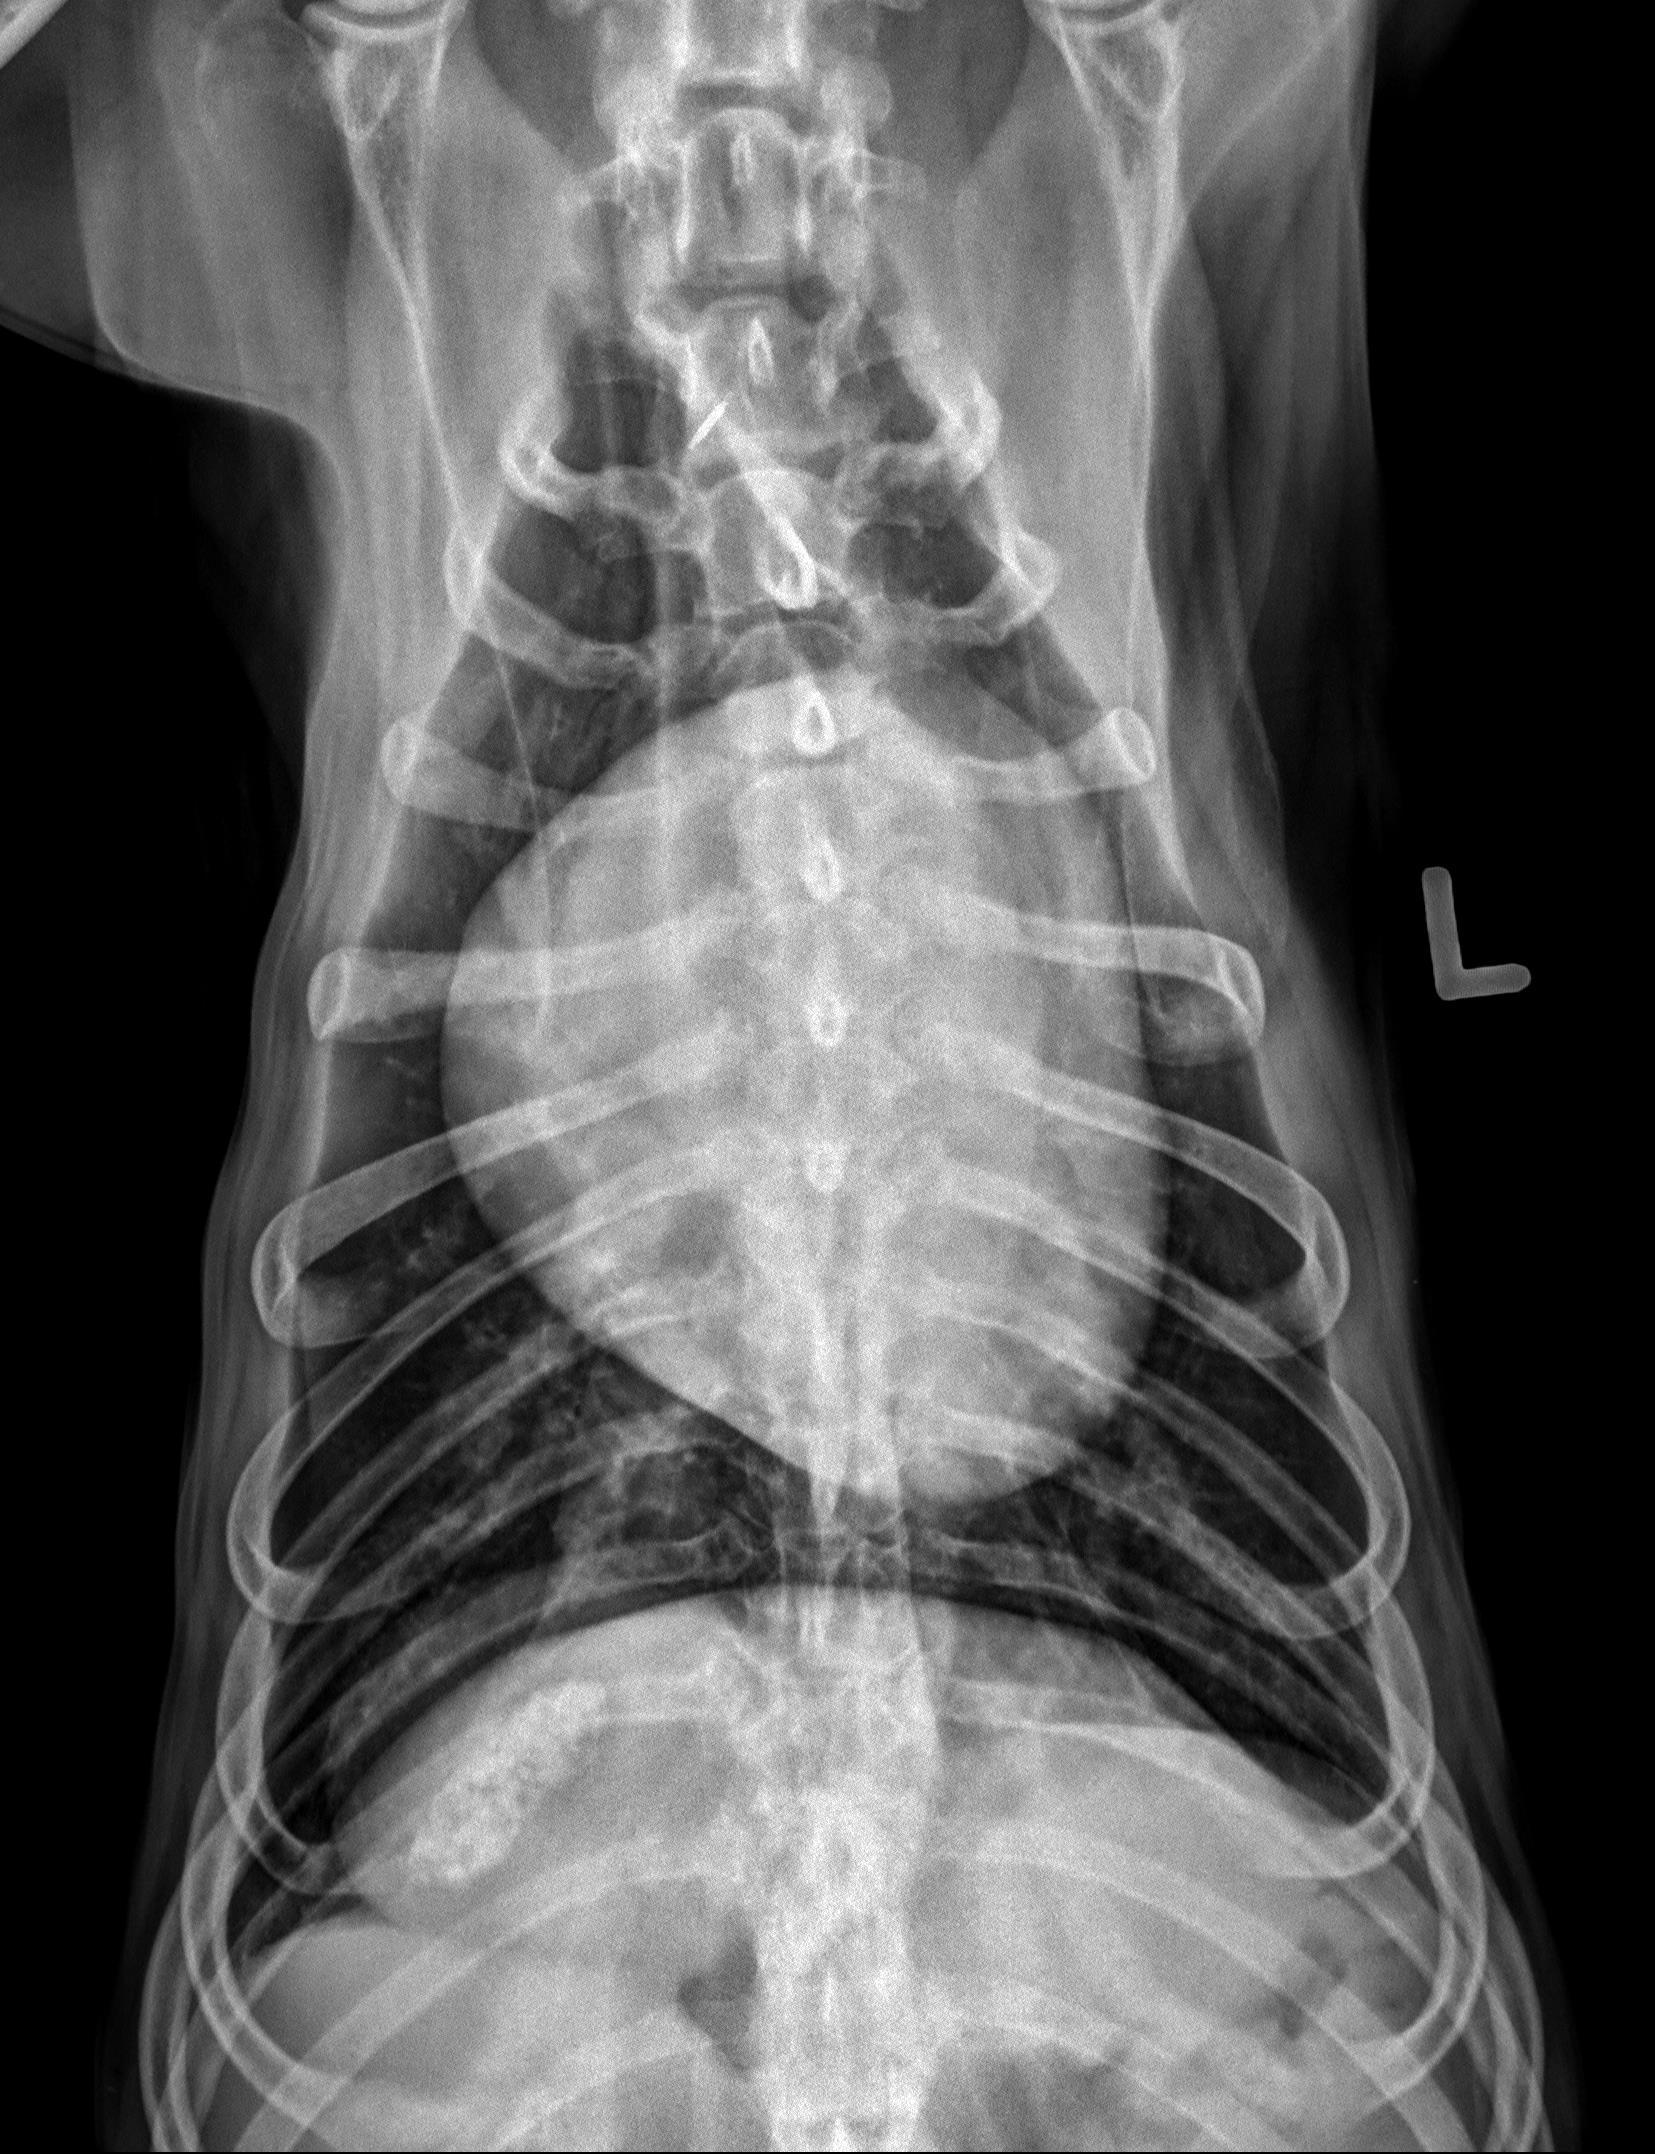

Thorax, 3 views:

There is an oval, well-circumscribed, soft tissue opaque mass associated with the most caudal dorsal aspect of the right caudal lung lobe. This mass measures approximately 7.0 x 7.0 x 6.6 cm (length X height X width) based on the left lateral and VD views (without correction for magnification).

There are additional multifocal pinpoint mineral opaque foci throughout the lung fields, consistent with incidental pulmonary osteomata.

The cardiovascular structures, mediastinal structures, pleural space, diaphragm, and thoracic wall are normal. There is incidental caudal thoracic spondylosis deformans.

There are sharply marginated but irregularly shaped regions of heterogeneous mineral opacity superimposed with the right cranial aspect of the liver as well as the right cranial abdomen (superimposed with the expected location of the proximal descending duodenum on the lateral views and visible in the plane of the right 11th intercostal space on the VD view).

On both lateral views, there are faint branching gas opacities superimposed with the cranial abdomen which appear to be located within the hepatic parenchyma.

Single large right caudal lobar pulmonary mass. A primary lung tumor (pulmonary carcinoma) is most likely. No evidence of pulmonary metastatic disease.

Granular mineral opacities in the plane of the right cranial abdomen are most consistent with mineralization within the gallbladder and common bile duct. Dystrophic mineralization of hepatic parenchyma, pancreas, and/or regional abdominal fat are considered as alternate but less likely etiologies. The branching gas opacities in the plane of the liver are likely associated with the intrahepatic bile ducts.